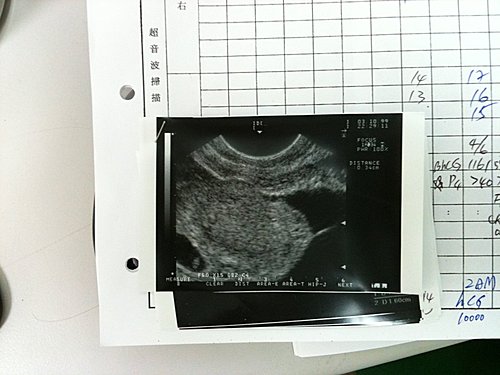

第一次看診3/10拿了6支針,第二次回診3/15拿了2次針,第三次回診3/17張醫師就告訴我3/19要取卵所以回去要打一支破卵針,第四次回診3/19取卵我只取到3顆(可能是我的卵開始老化了,但是張醫師安慰我說只要有1顆健康的卵,就有實現夢想的機會),第五次回診3/22殖入,之後拿一些黃體素回家打(有點痛),到4/6號就等待開獎,結果我真的懷孕了,我從沒這麼幸運過一次就成功了,這一天是我跟我老公重生的日子,因為這十年來我們每個月都期待,得到的卻只是一次又一次的失望